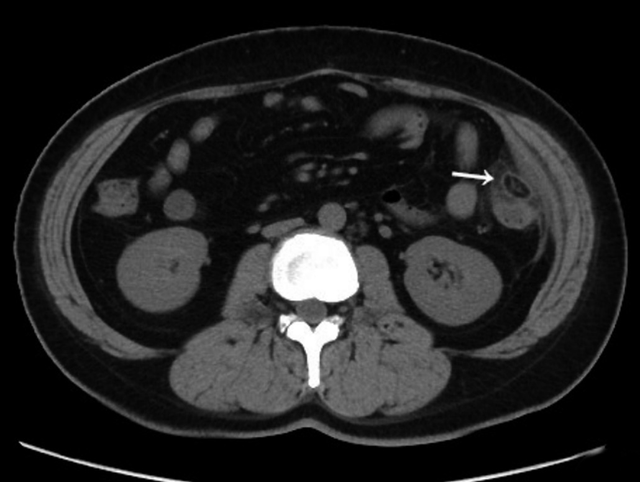

原发性肠脂垂炎有没有是一种自限性疾病,可以自愈,并不需要治疗(考虑到当下的医疗小腹环境,也可以采取对症治疗)。如果是其他疾病的并发症所致的肠脂垂炎,我们需要对原发病进行治疗。肠脂垂炎区域,脂肪密度增高区、团块影,最后变小、吸收;如果不能完全吸收,肠脂垂可脱落,发生钙化。

前图为肠脂垂炎发病期,后图为肠脂垂脱落发生的钙化(在影像学中,该变大钙化称为“腹腔鼠”),小腹淋巴在哪个位置图片。